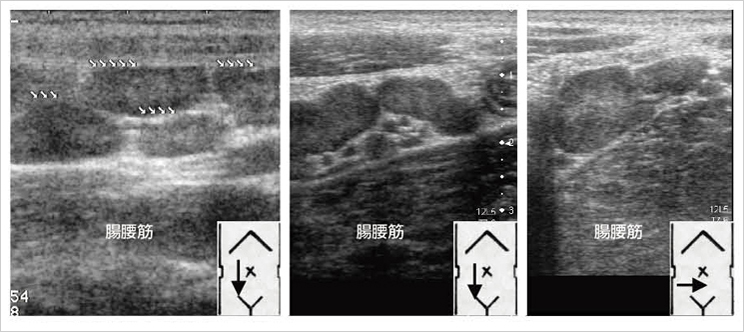

急性虫垂炎のエコー診断の副産物として,腸間膜リンパ節炎や急性腸炎のより正確な診断が可能になってきた。すなわち,腫大虫垂が描出されず,回腸末端壁の肥厚(図8),腸間膜リンパ節の腫大(図9),回盲弁の肥厚(図10),大腸壁の肥厚(図11),小腸や大腸への液の貯留,腹水の存在などの所見を臨床症状・検査所見・診察所見に加味することで回腸末端炎,急性大腸炎,腸間膜リンパ節炎のより正確な診断が可能で,事実に基づいた診療へと変化している。

図8 回腸末端壁肥厚の3例

図9 腸間膜リンパ節腫大の3例